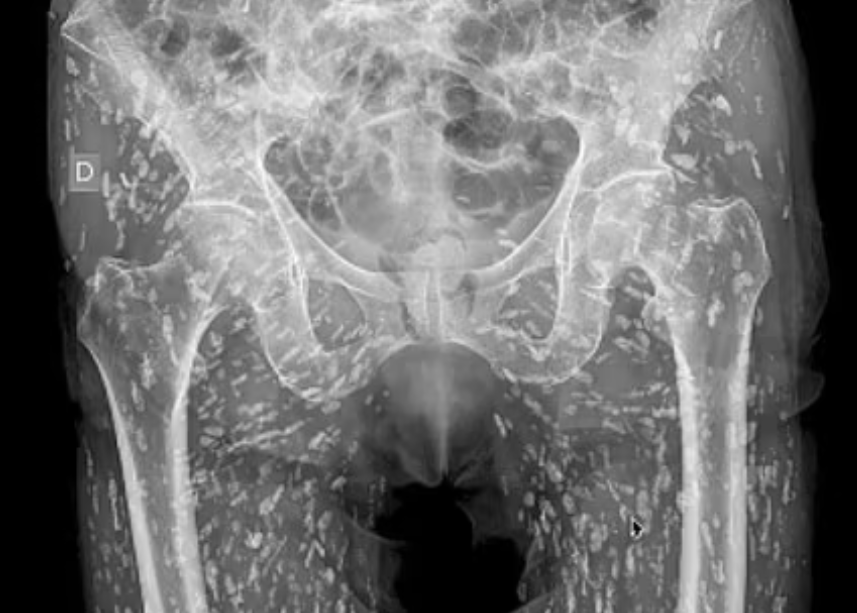

The image shows hundreds of 'rice grain' nodules that turned out to be cysts caused by the parasitic infection.

In a video that has went viral, a shocked Dr Ghali says: 'They're everywhere [the cysts] and they're innumerable, you can't even begin to count them all.

'Now these cysts can travel anywhere throughout the entire body. In this patient, they've traveled heavily to the soft tissues of the hips and the legs.'